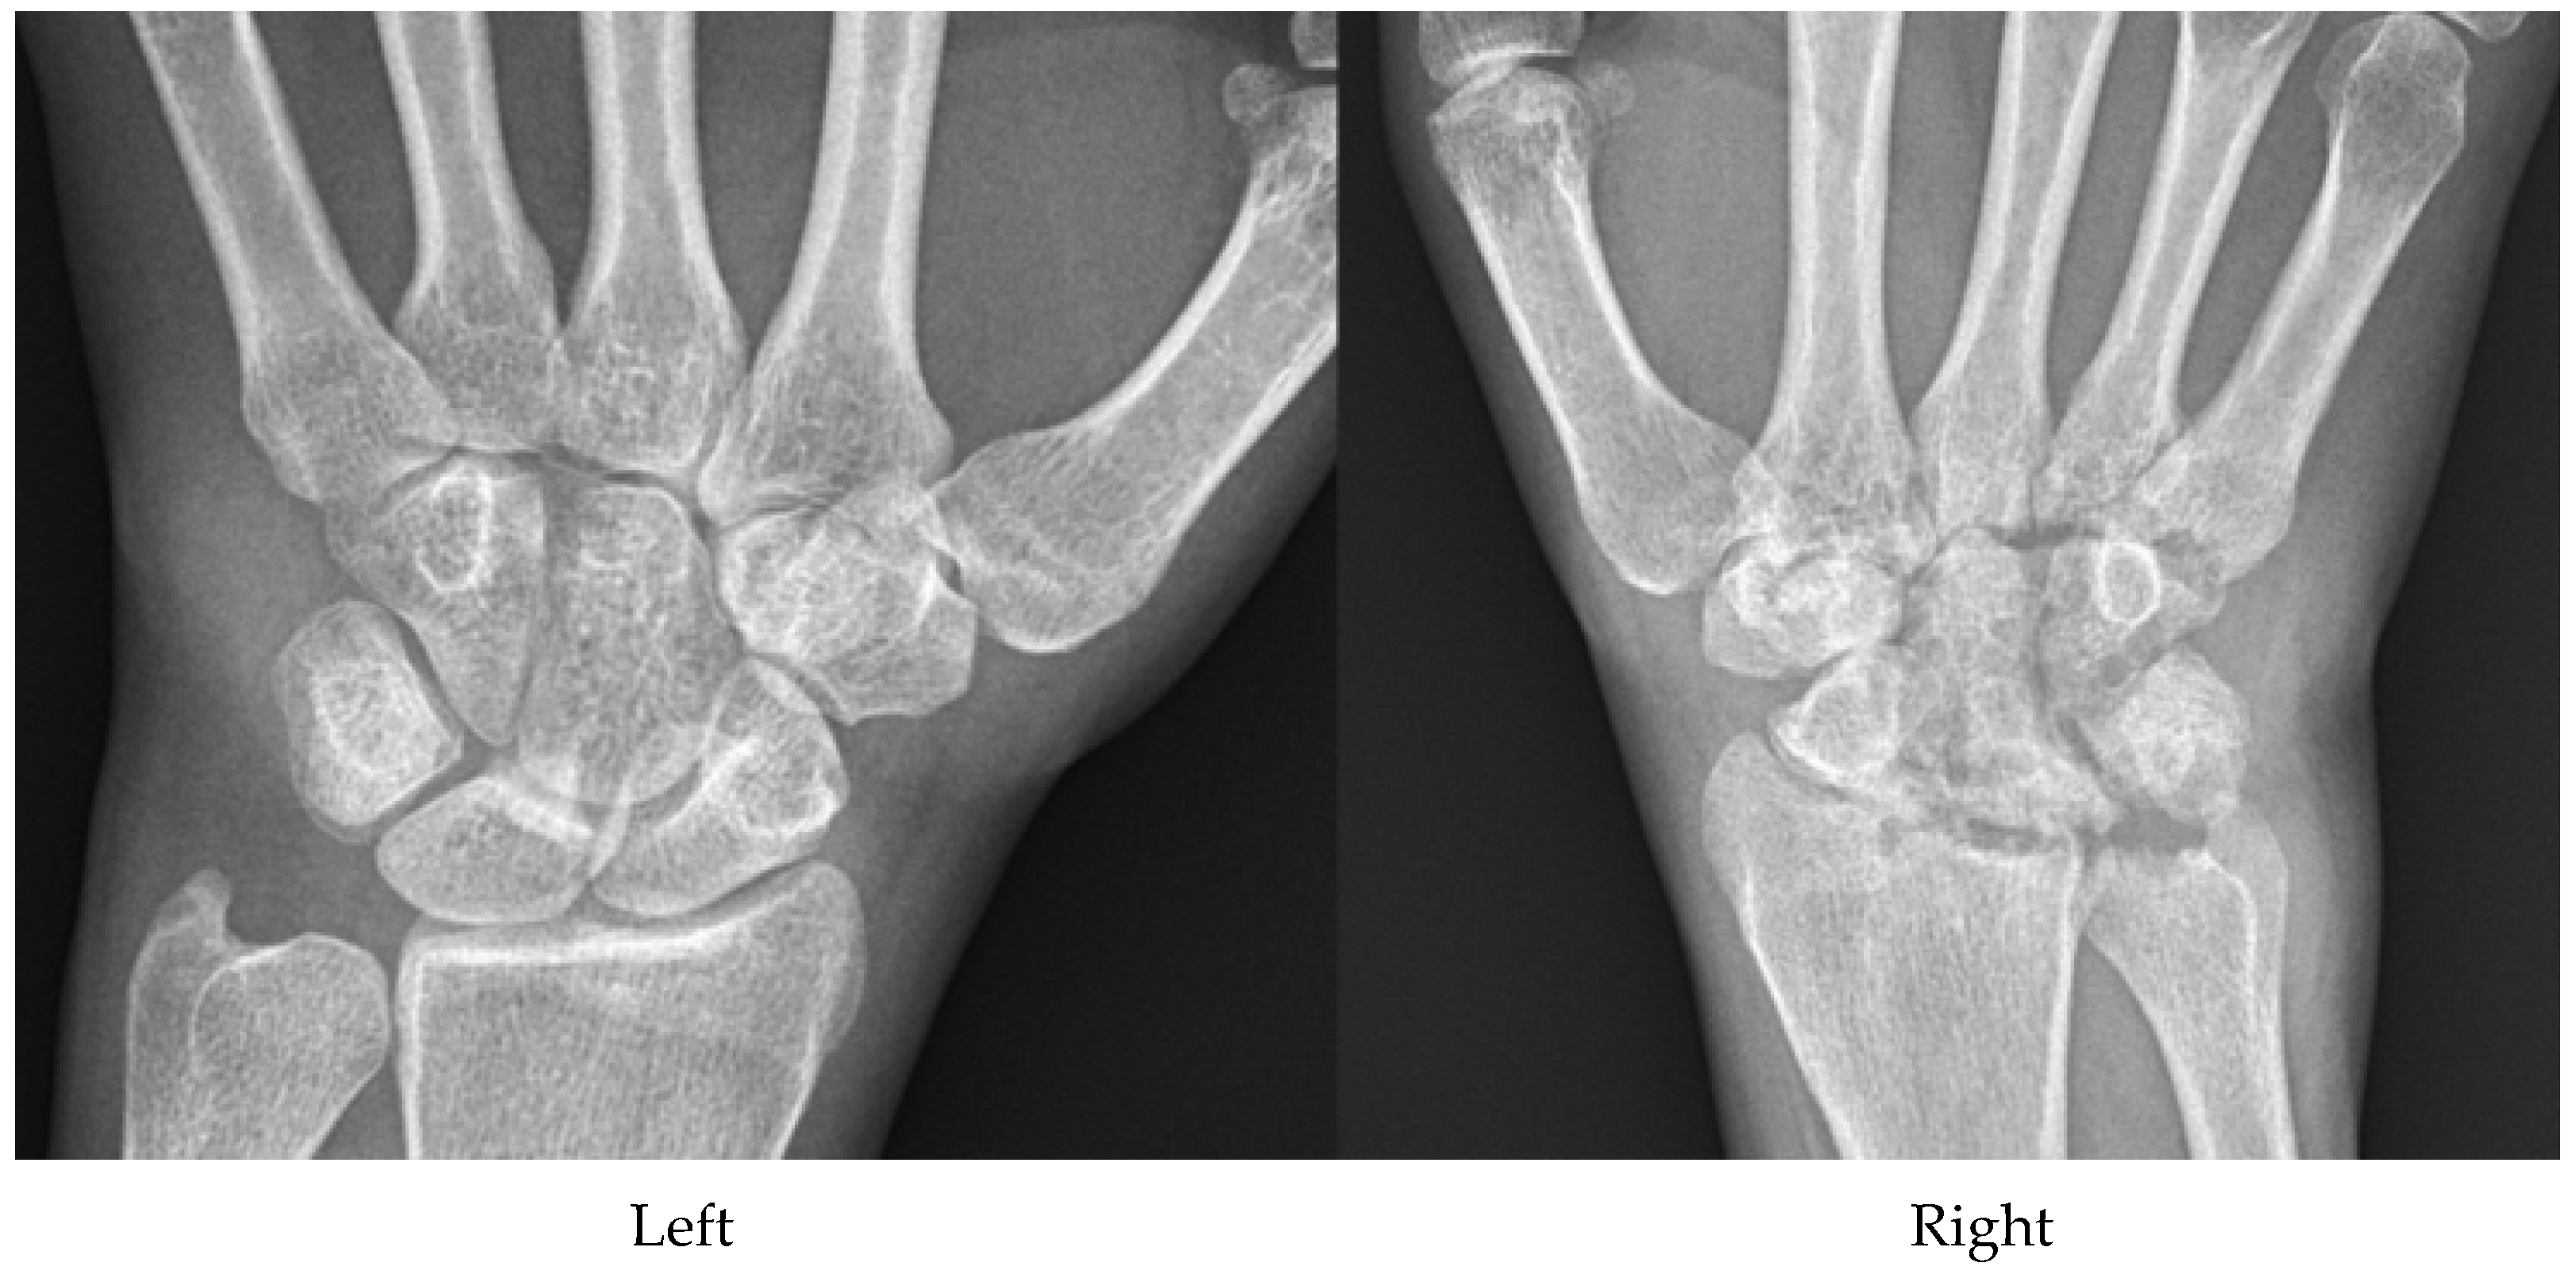

7. Calcium Pyrophosphate Dehydrate Arthropathy (CPPD)